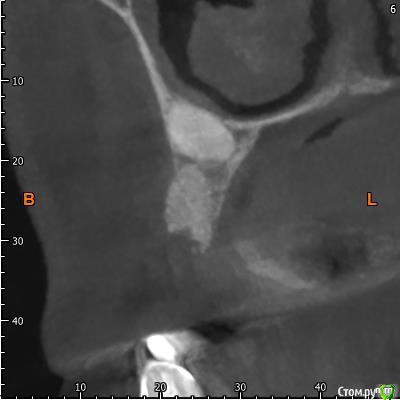

Павел7809 Опубликовано 9 апреля, 2018 Поделиться Опубликовано 9 апреля, 2018 Собственно ситуация такая. Предстоит каким то образом удалить ретенированный клык. Находится в небе, да и еще кривым апексом который торчит в носу. Полгода назад этому же пациенту почти такой же клык я удалил, но там как то все проще было по топографии. Собственно , господа, как и чем? Возможны ли какие то кровотечения носовые и тд. Кто сталкивался? Может как то распилить его со стороны щеки пополам и вытащить.. Ссылка на комментарий

Павел7809 Опубликовано 9 апреля, 2018 Автор Поделиться Опубликовано 9 апреля, 2018 Может так получше. Орто нет... Ссылка на комментарий

Павел7809 Опубликовано 9 апреля, 2018 Автор Поделиться Опубликовано 9 апреля, 2018 Так все тоже самое:Анестезия.Разрез.Декоронация.Удаление корня.Кюретаж.Швы.В нос провалитесь - плохо, но не страшно, будет кровать, тампонада носового хода.Я ведь правильно понимаю - сначала надо будет отрезать крючек со стороны щеки, сделав к нему окошко на уровне апексов 6 ки а потом удалить все остальное через небный доступ? Ссылка на комментарий

Борис80 Опубликовано 10 апреля, 2018 Поделиться Опубликовано 10 апреля, 2018 я бы вестибулярно делал, окно в области коронковой части, чуть апикальнее может, коронку отпилил, корень вывихнул Ссылка на комментарий